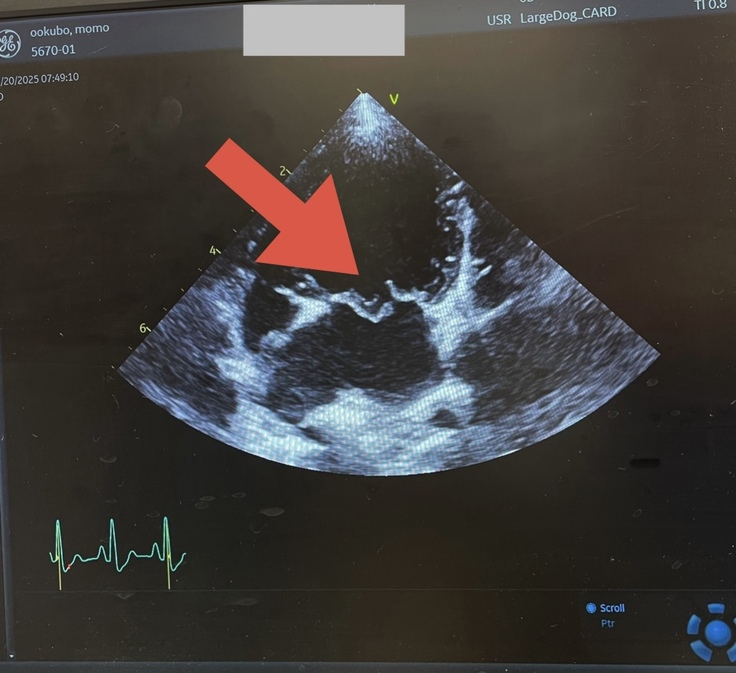

■僧帽弁閉鎖不全症【ステージD】(最終段階)

心臓肥大:2.5

※LA/Ao値(正常:1.2〜1.5)↗

E波:1.5 m/s

※血液の流入速度(正常:1.0〜1.2)↗

■三尖弁閉鎖症

▼ももたんの病気「僧帽弁閉鎖不全症」とは?

心臓には全身に血液を送る「ダム」のような部屋があり、水門(=僧帽弁)がきちんと閉まることで、一方向に血が流れます。

でも、ももたんの水門は壊れてしまい、血液がすごい勢いで逆流(E波:1.5)。

その結果、心臓は正常値を大きく上回り肥大(LA/Ao値:2.5)、気管や肺を圧迫するようになっていました。

逆流した血液は肺へ押し戻され、水分が血管からしみ出すことで「肺水腫」を引き起こします。

肺水腫は、肺の中の組織が水浸しになり、呼吸がうまくできなくなります。

肺水腫を繰り返すたびに命を落とす確率は20〜30%。

ももたんは、すでに初期の肺水腫を起こしており、心臓の状態も非常に悪いため、いつ重度の肺水腫を起こしてもおかしくない状況です。さらに、ナトリウム値が低く、利尿剤が効きにくい体質。

このため、内科治療の効果が得られず、ステージD 【余命4か月】と診断されました。

▼僧帽弁(ダムの水門)が閉じていない